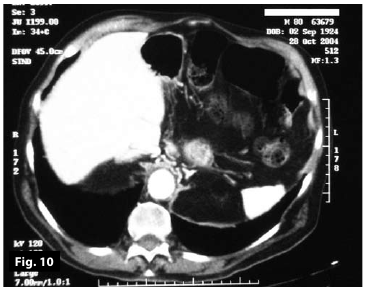

Figure10

Figure9-10